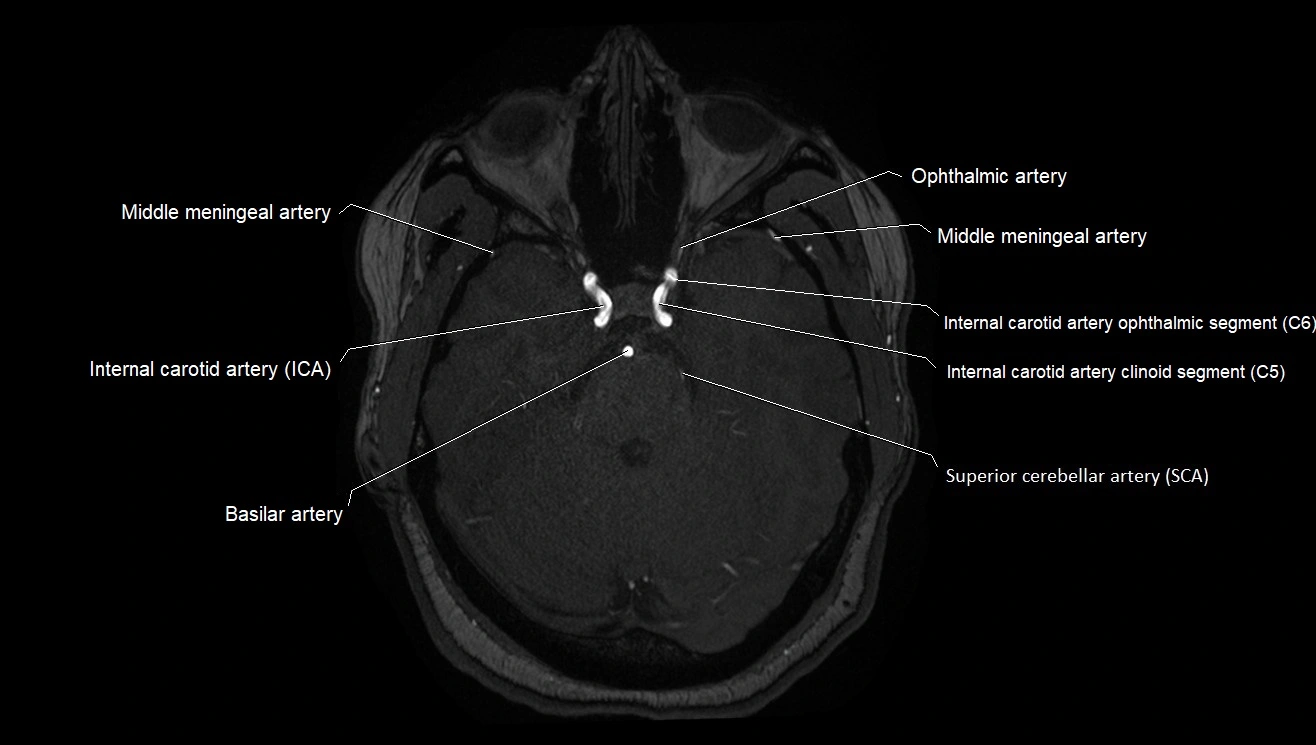

MRA (Magnetic Resonance Angiography):

• Flow-related enhancement makes the AChA appear as a bright, linear vascular signal against suppressed background

• High sensitivity for origin and proximal course; distal branches may be too small to resolve

• Detects stenosis, occlusion, aneurysm, AVM feeders

MRI images

image